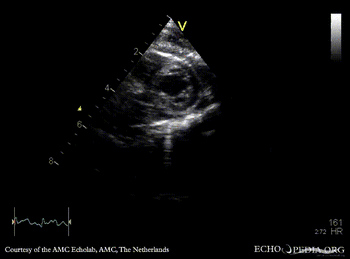

| Courtesy of: AMC Echolab, AMC, The Netherlands | |

| PSAX | |